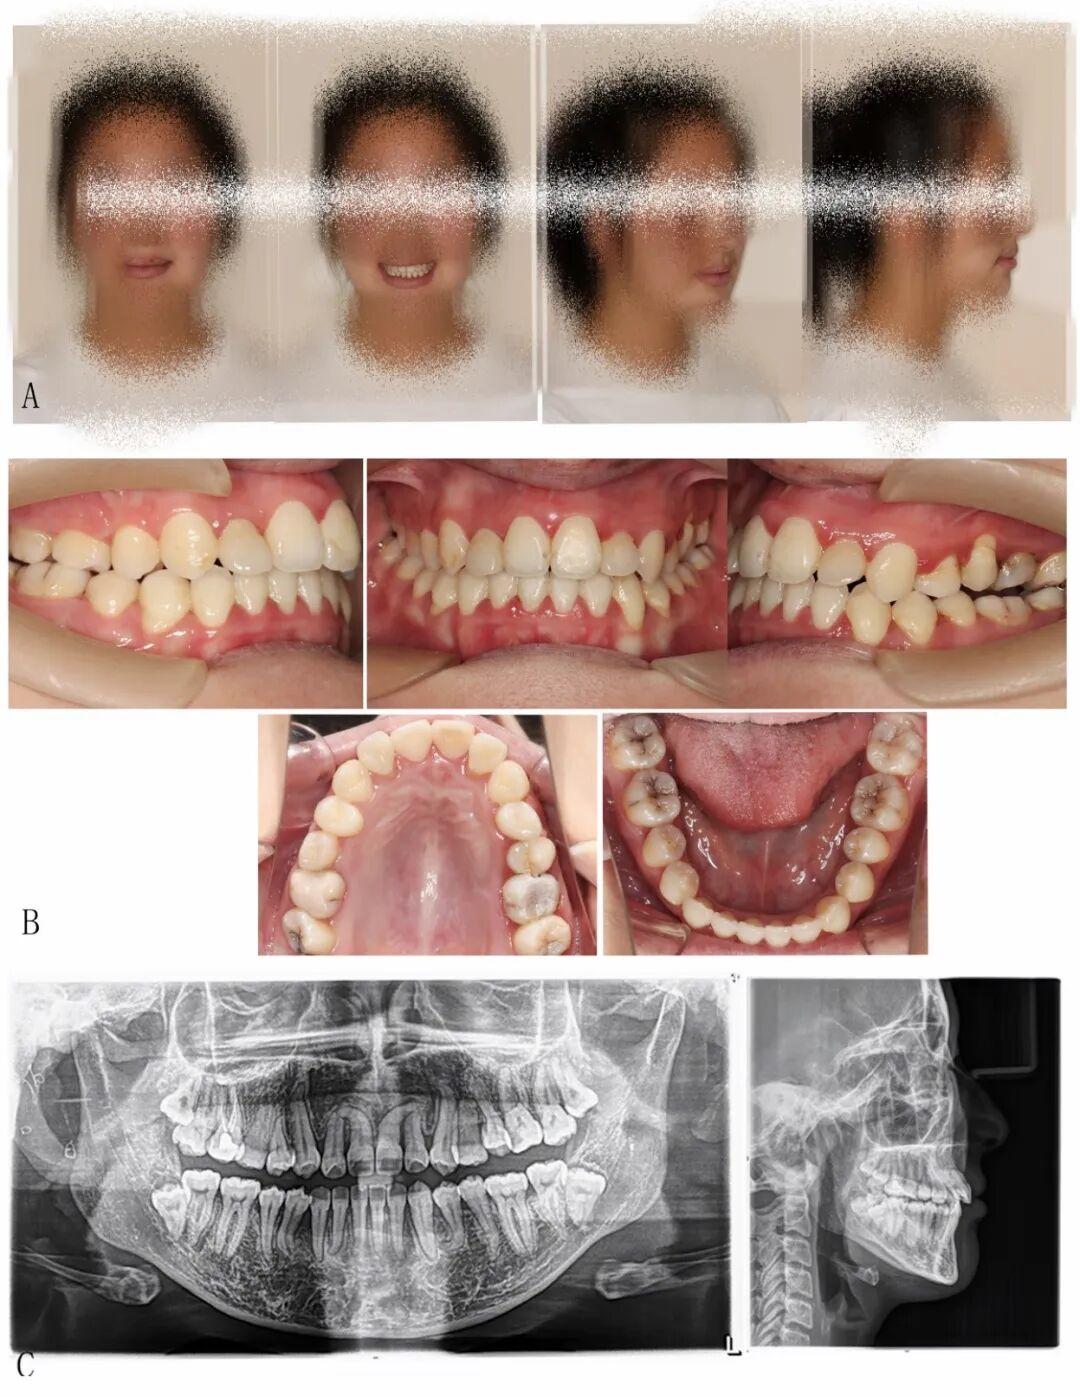

图1:治疗前面相(A)、口内相(B)、曲面断层片、头颅侧位片及胸片(箭头处为怀疑锁骨缺如处)(C)

这就造成了,曲面断层片上,牙齿纵横交错,情况非常复杂!

同时,X光片还提示伴有面部不对称等,这些全身特征高度指向一种罕见的遗传性疾病:颅骨锁骨发育不全综合征(CCD)。